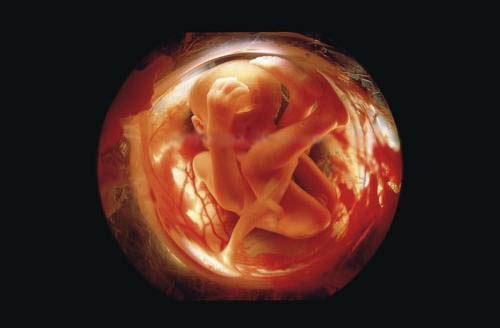

Предлагаю Вашему вниманию уникальный репортаж из женского тела.

Эти уникальные фотографии сделаны шведским фотографом Леннартом Нильсоном ещё в 1965 году. Сам фотограф родился в 1922 году и стал первым, кто при помощи специального оборудования и фотокамер, смог проникнуть внутрь женского тела и снять весь процесс зарождения новой жизни.

Первые фотографии эмбриона появились в печати ещё в 1953 году, и это событие вдохновило фотохудожника на создание новых работ.

Для того, чтобы показать развитие человека с самого начала, он поместил микрокамеру и микроосветитель на конец трубки цистоскопа, которым осматривают мочевой пузырь, и снял свои уникальные фотографии прямо оттуда, откуда люди делают первый шаг в мир...

Вот она - наша история зарождения жизни!